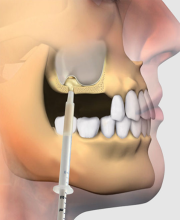

2. درمان بدون درد:

با استفاده از تجهیزات پیشرفته و بیحسیهای عالی، ما تضمین میکنیم که جراحی دندان نهفته بدون احساس درد و در کمترین زمان ممکن انجام شود.